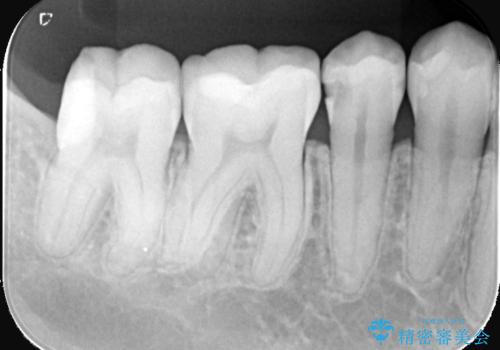

見落としやすい虫歯(コンタクトカリエス)を発見|精密診断で早期治療

- 患者様は特に痛みはなかったものの、定期検診で虫歯がないか確認したいとのことで来院されました。視診では明らかな虫歯は見当たりませんでしたが、レントゲン検査で歯と歯の間(コンタクトポイント)に虫歯(コンタクトカリエス)を発見。この部分の虫歯は初期では自覚症状が少なく、発見が遅れると治療範囲が広がることがあるため、早期に適切な治療を行う方針としました。